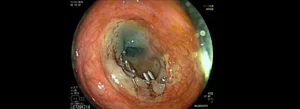

Στη συνέχεια, ο γιατρός παγιδεύει τον πολύποδα με έναν ειδικό βρόγχο και τον αφαιρεί, είτε με τη χρήση ηλεκτρικού ρεύματος (hot EMR) είτε χωρίς (cold EMR), στέλνοντάς τον για βιοψία. Τέλος, αν κριθεί απαραίτητο λόγω του μεγέθους ή της θέσης της τομής, τοποθετούνται μεταλλικά κλιπ για να κλείσει η πληγή και να αποφευχθούν μελλοντικές επιπλοκές.

![]()